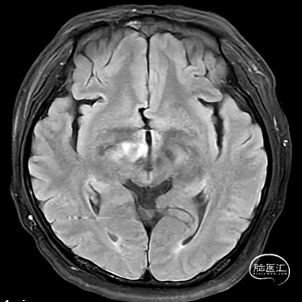

1.右侧大脑脚-右侧丘脑急性脑梗死。

右侧中脑-丘脑可见新发脑梗塞:

颅内外血管未见明显狭窄。

CT(CTA)检查提示:右颈内动脉C7段大小约3.6×3.8×3.6mm及基底动脉远端动脉瘤形成大小约9.7×7.6×9.3mm。